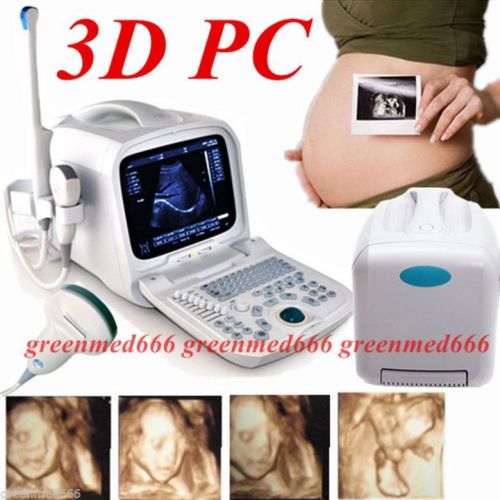

| Model | RUS-9000F |

3D PC platform Full Digital Portable Ultrasound Scanner + Transvaginal Probe FDA